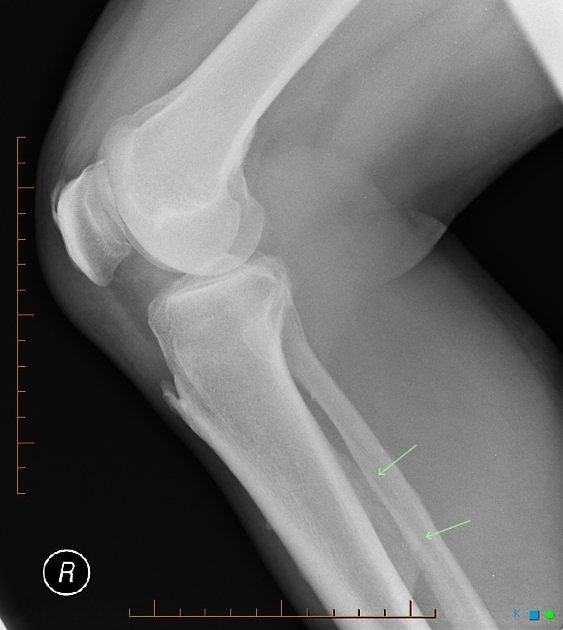

Рентгенография выявляет следующие признаки периостита:

Утолщение и уплотнение периостальной полосы по наружному контуру кости, сигнализирующее о воспалительной реакции надкостницы.

Наложение слоёв новообразованной костной ткани (периостальных наслоений) в виде однослойного или многослойного утолщения, что отражает стадию процесса.

Неровность и шероховатость наружного края кортикального слоя под зоной периостальной реакции, указывающая на перестройку поверхности кости.

При хроническом течении — грубые наслоения с образованием периостальной «шишки» или кортикальной утолщённой манжеты.

При остром периостите — мягкотканевая припухлость с незначительным размытием мягкотканевой тени на стороне поражения.